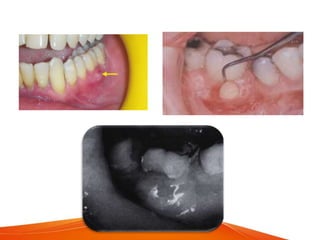

Periodontal abscess

of the gingiva along the lateral aspect of the root.

• The gingiva is edematous and red, with a smooth, shiny

surface. The shape and consistency of the elevated area vary;

• In most cases, pus may be expressed from the

• An acute periodontal abscess without any notable clinical

• The chronic periodontal abscess usually presents draining

sinus along the lateral aspect of the root.

• The sinus may be covered by a small, pink, beadlike mass of

granulation tissue.

Sinus

Sinus orifice from a buccal

A. Pinpoint orifice in the buccal side

B. Probe extends into the abscess deep in